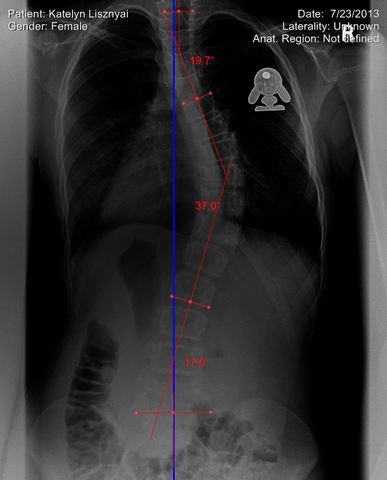

• Diagnosed with Scoliosis

Diagnosed with Scoliosis

At dance class one night in Charlotte, I was stretching when my dance instructor noticed a small hump developing on the right side of my back. She told my mother and I that it was probably scoliosis. Sure enough, when my mother took me to the doctor for an x-ray, we noticed that I had a minor curve in my spine. At this point, I could have had surgery, but I would have multiple surgeries because I was so young. So, I decided to not have the surgery until later and start chiropractic treatment

• First Day of Intensive Therapy

After being diagnosed with scoliosis, I tried bracing. I had to wear a back brace for many hours a day until I got to a point where I would have had to wear it for 23 hours a day. This was too much. That was when I found Maximized Living and their intensive scoliosis therapy. I went down to sunny Orlando, FL for a week on hard and painful stretching and pulling. However, the treatment was able to reduce the curvature of my spine anywhere from 8-12 degrees. I continued this treatment for 5 years.

This was one of the hardest decisions I have ever needed to make in my life. My scoliosis had gotten to a point that at one of my dance competitions, I overheard a judge telling my dance instructor, "Sorry to see the girl with the broken arm." This was because the the giant hump on my back. This caused my arm to bend in a weird shape. At this point, I knew it was time to quit and move on to another chapter in my life.

• Back Surgery

Back Surgery

My back got to a point that my spine started to impact my lung capacity, therefore effecting the way I breathe. This is when I was told that I would need the surgery. Thankfully I only needed one. However, this was a very traumatizing experience. I came out stronger on the other side. I am a lot better physically and mentally now than I was before.